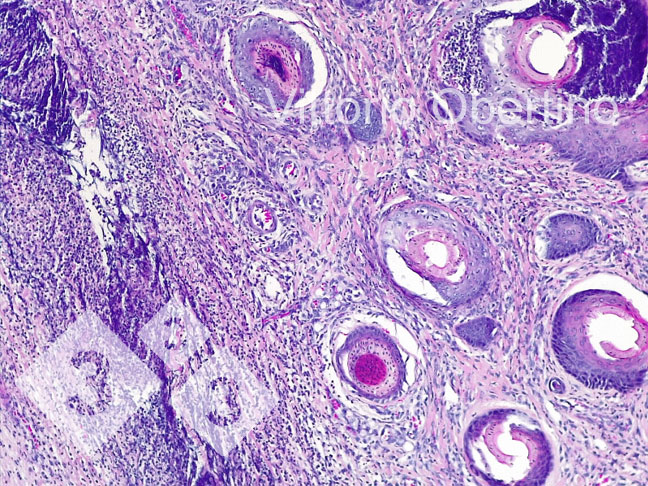

2- Amostras de tecido foram enviadas à Universidade de Torino para verificar se as lesões eram histologicamente compatíveis com as imagens descritas na literatura (Kuehling et al. 2020).

- A presença de lesões clínicas e o quadro histológico.